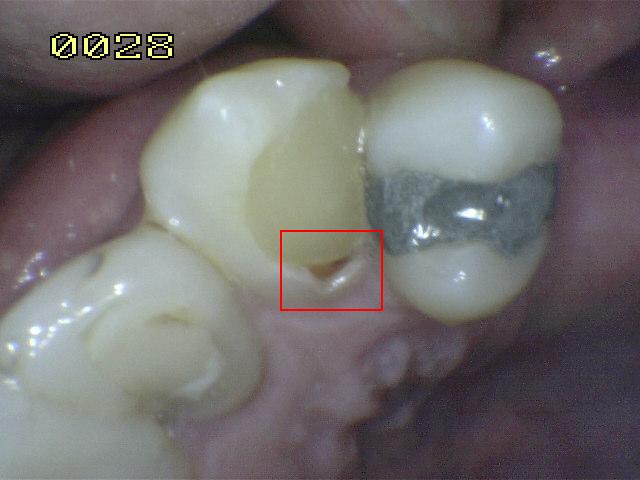

Código 2

(Caries Inicial): Lesión de

caries observada en esmalte en estado húmedo y permanece después de

secar.

- Si el margen de la

restauración está en esmalte, se debe observar el

diente húmedo. Cuando esta húmedo hay una opacidad

compatible con la desmineralización o pigmentación

que no corresponde a la aparencia clínica del

esmalte sano (Nota: la lesión sigue siendo visible

cuando se seca).

- Si el margen de restauración está en dentina: el

Código 2 corresponde a la pigmentación que no es

compatible con la aparencia clínica de la dentina o

el cemento sano.

- (Mancha blanca

/ marrón)